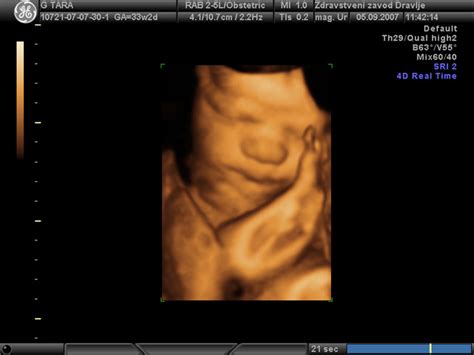

Nosečnost je dinamičen proces, ki se ga je dobro naučiti razumeti. Tečaji, kot je "Tečaj zgodnje nosečnosti", ki poteka med 12. in 18. tednom nosečnosti, ponujajo celosten vpogled v potek nosečnosti in razvoj ploda. Takšno predavanje, ki ga vodita diplomirana babica in kineziologinja, ponuja strokovne informacije o tem, kaj se dogaja z vašim telesom in otrokom v tem ključnem obdobju. Pomembno je, da se seznanite s potrebnimi preiskavami in pregledi, ki zagotavljajo spremljanje zdravja vas in vašega naraščajočega otroka. Poleg tega tečaji poudarjajo pomen zdravega načina življenja, ki vključuje ustrezno prehrano in redno, a varno telesno aktivnost. Razumevanje zakonitosti in poteka razvoja dojenčka od rojstva do samostojne hoje je ključno za zgodnje sodelovanje z njim. Spoznavanje, kako je bilo v družinah nekoč, lahko ponudi zanimiv kontekst za sodobne pristope k starševstvu.